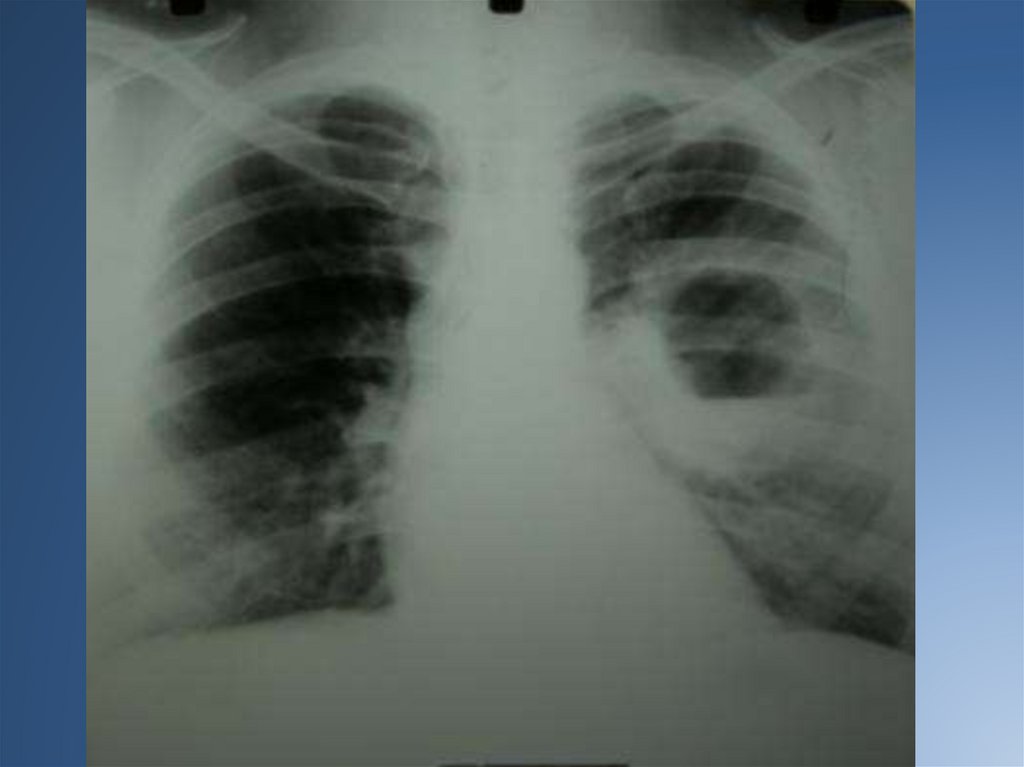

На рентгенограмме рисунок легких носит сотовый или ячеистый характер, иногда

выявляются полостные образования, вокруг которых могут быть воспалительные

инфильтраты.